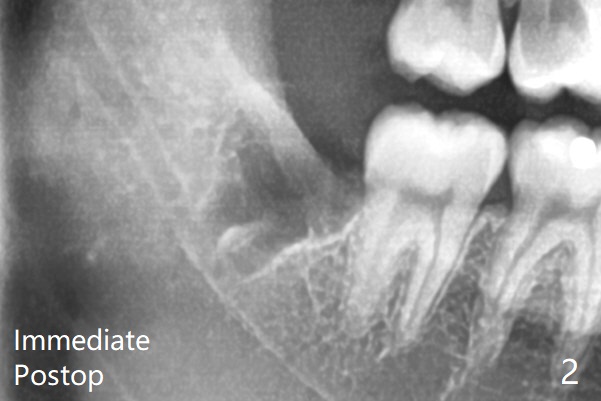

To prevent dry socket, collagen plug is placed at #17 and 32 post extraction (Fig.2).